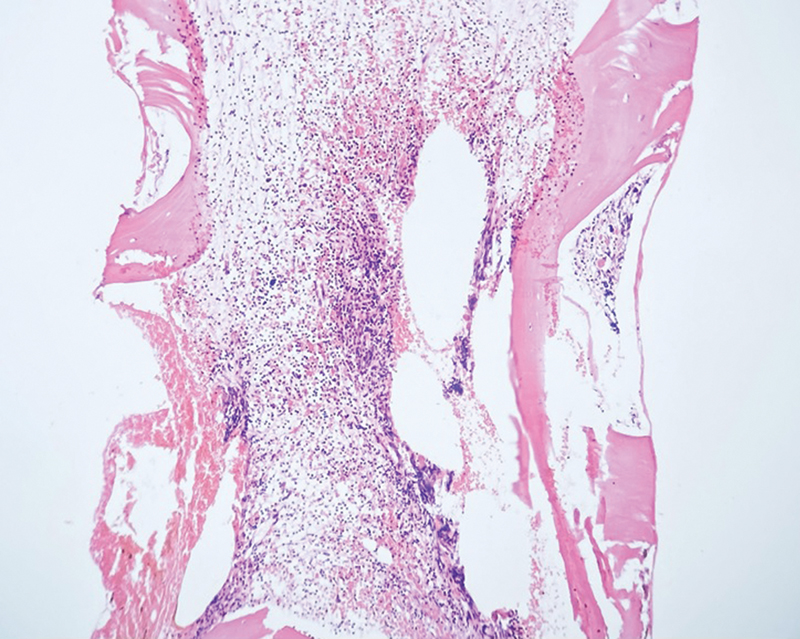

Initial examination was unremarkable except palpable hepatomegaly 2 cm below the right costal margin. There was no lymphadenopathy or other significant findings. Preliminary investigations were similar to outside reports, with no abnormal cells noted on peripheral smear. Liver and renal function tests and autoimmune markers were negative. A bone marrow examination was repeated, which again resulted in a dry tap. Trephine biopsy revealed a hypocellular marrow with a cellularity of 10 to 20%. associated with absent megakaryocytes and grade 2 to 3 reticulin fibrosis ([Figs. 1] and [2]). On further sections, interstitial infiltrates of small-sized lymphoid cells with round, clumped chromatin and inconspicuous nucleoli were noted. These cells were positive for CD20 and BCL2, and negative for CD5, CD10, BCL6, annexin A1, cyclin D1, and TdT on immunohistochemistry (IHC). Fluorescent in situ hybridization (FISH) panel for MDS and next-generation sequencing (NGS) for myeloid mutations were initially sent, both of which were negative.

Fig 1: Bone marrow trephine biopsy showing a hypocellular marrow with approximately 10